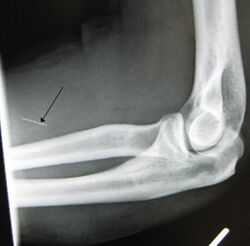

- Arterial damage – Arterial pseudoaneurysms may form at injection sites, which can rupture, potentially resulting in hemorrhage, distal ischemia, and gangrene. Inadvertent intra-arterial injection can also result in endarteritis and thrombosis, with ultimately similar consequences.[3]

The preferred injection site is the crook of the elbow (i.e., the Median cubital vein), on the user's non-writing hand. Other users opt to use the Basilic vein; while it may be easier to "hit", caution must be exercised as two nerves run parallel to the vein, increasing the chance of nerve damage, as well as the chance of an arterial "nick".[5]

Drug injection is also commonly a component in HIV-related syndemics. Fragments from injection of pills are known to clog the small blood vessels of the lungs, brain, and elsewhere, potentially causing pulmonary embolism (PE), stroke, or venous embolism. A small proportion of PE is due to the embolization of air, fat, and talc in the drugs of people who inject substances. More commonly, the inflammatory response to these foreign objects causes granulation tissue to form in the capillary beds, resulting in vasculitis, and, when it occurs in the pulmonary capillary bed, potentially pulmonary talcosis. Hitting arteries and nerves is dangerous, painful, and presents its own similar spectrum of problems.